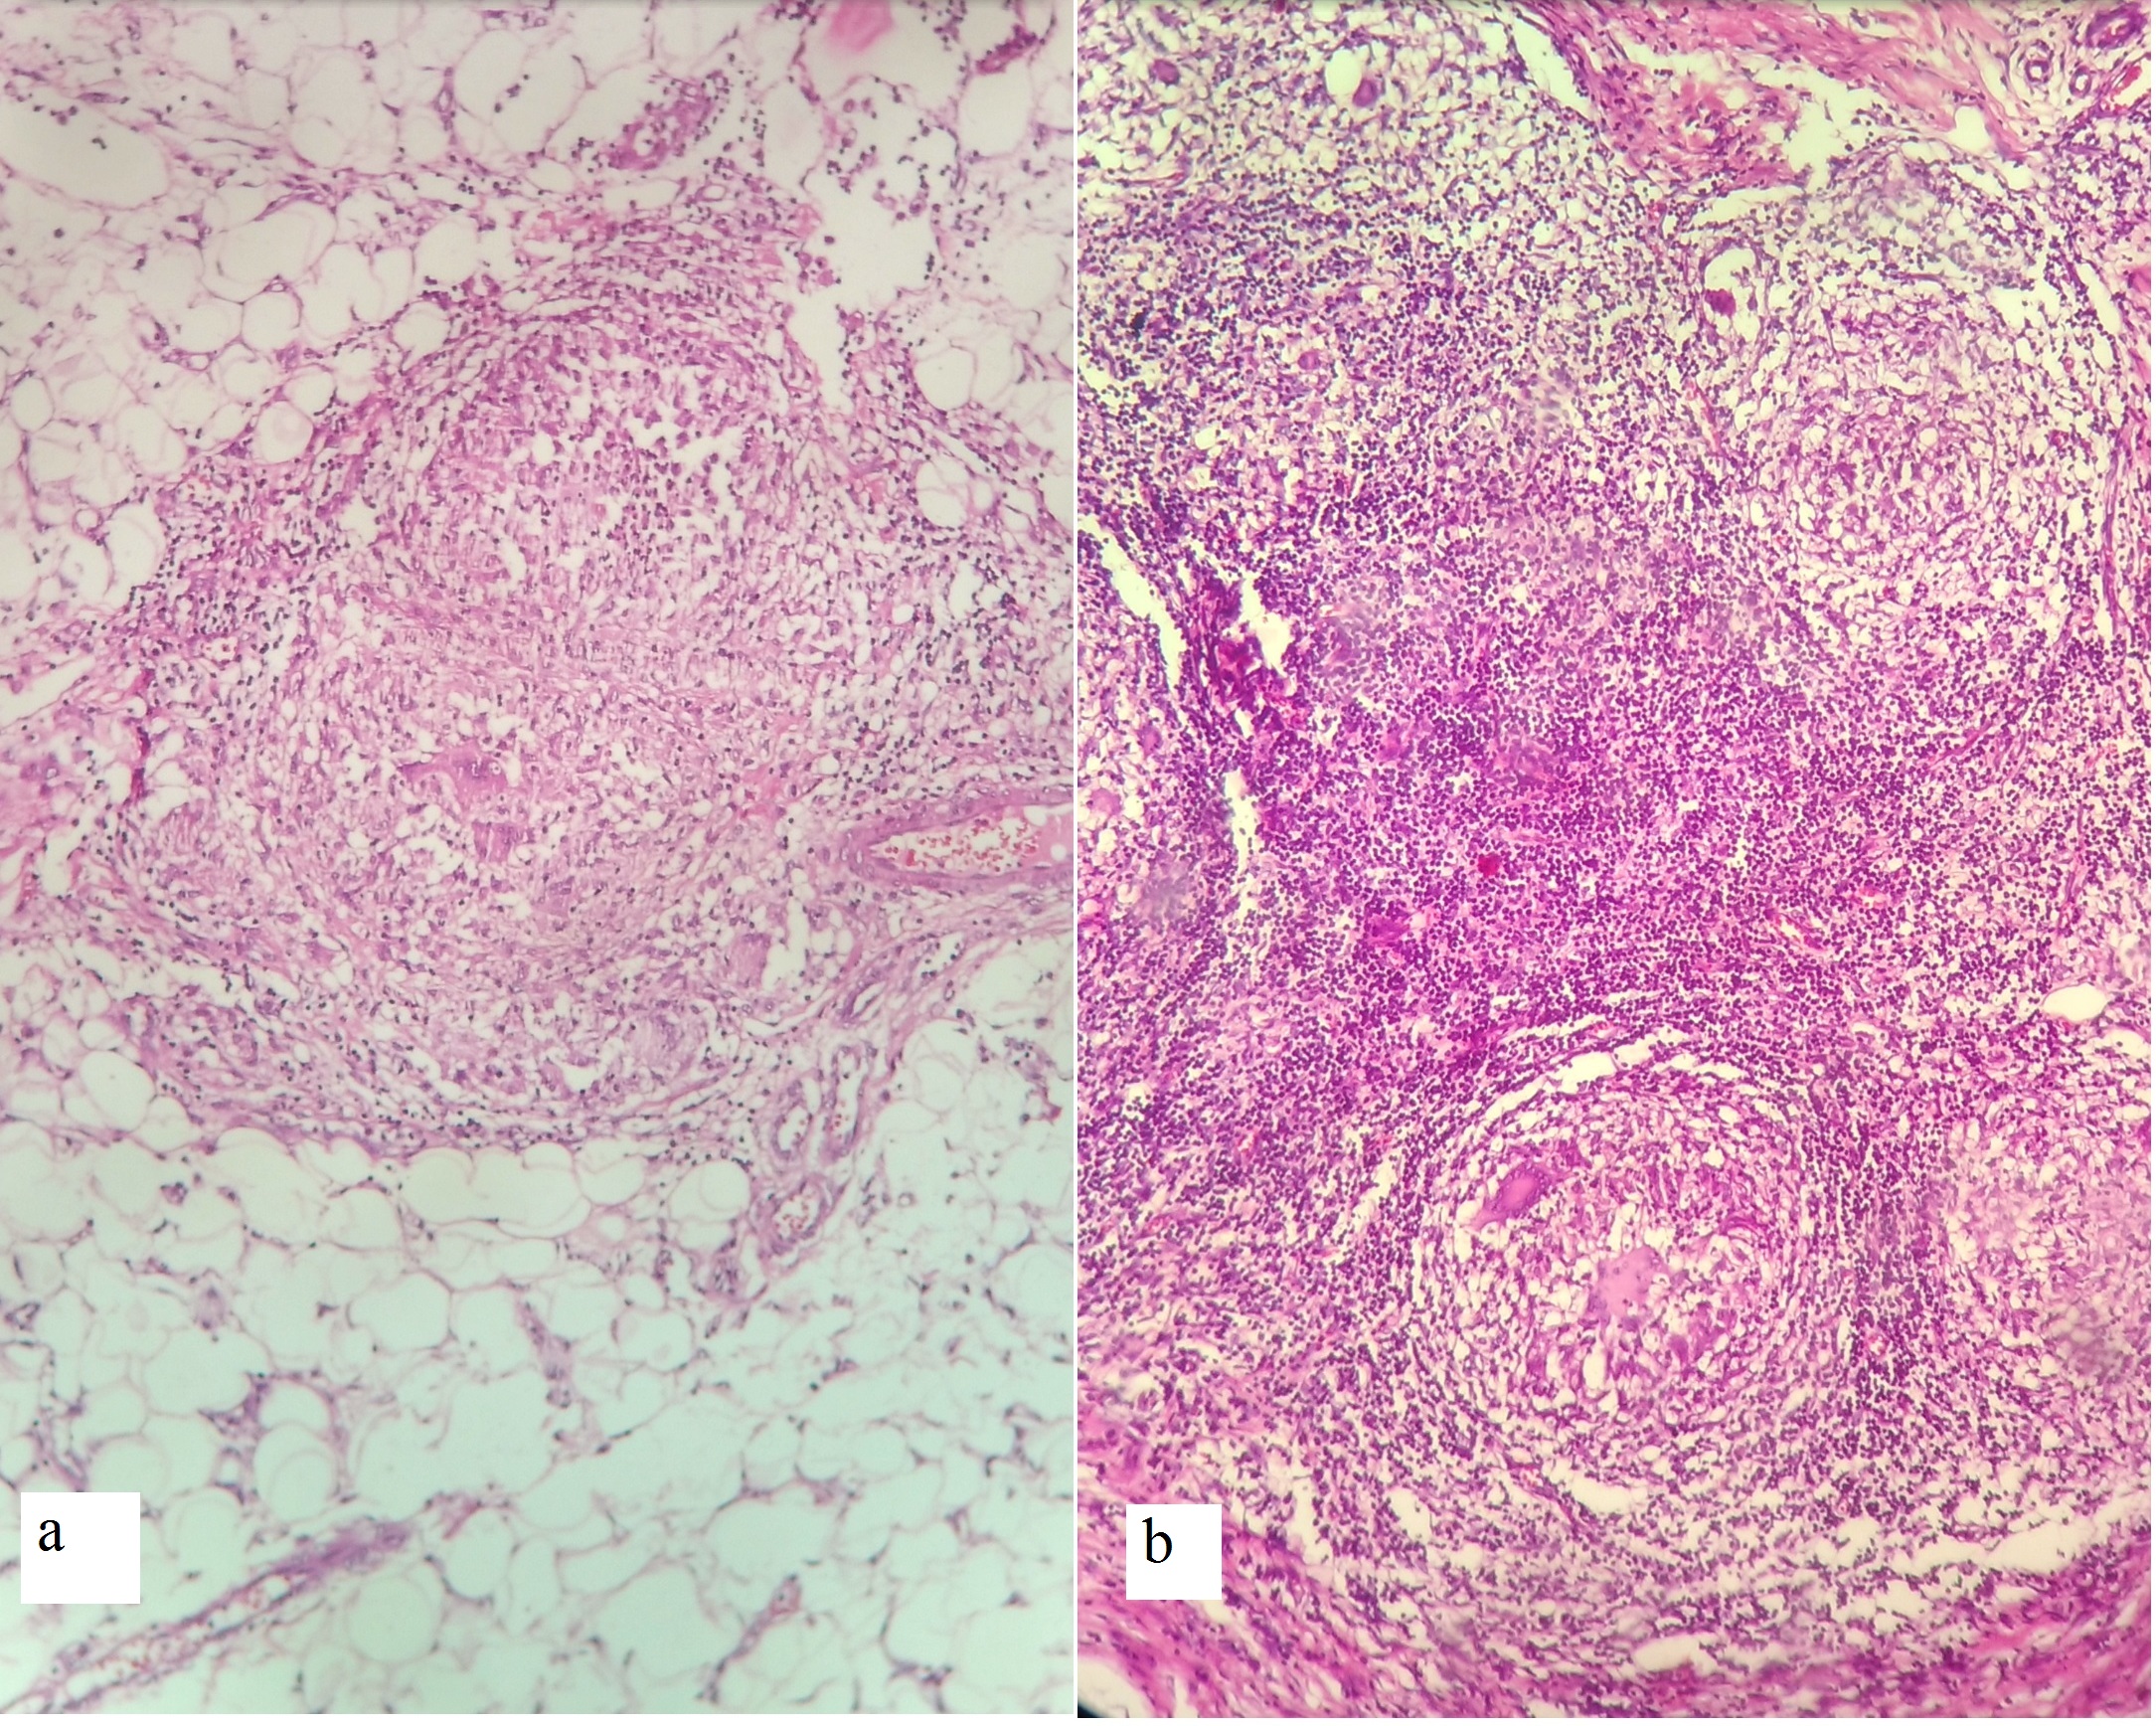

Results. A total of 17 patients presented to the emergency ward with features of acute intestinal obstruction. The average age was 15.3 years (range 9 years to 16 years). There were 14 females and 3 males. All patients presented with abdominal pain, bilious vomiting, constipation and abdominal distention. The patients were operated in our hospital and relieved of their obstruction. Based on their operative findings and after histopathological confirmation, patients were given ATT. In the follow-up, all patients did well, without recurrence of tuberculosis or intestinal obstruction.

Conclusion. Tuberculosis as a cause of childhood AC is rather common in developing countries and is potentially a fatal condition. A strong clinical suspicion, sonographic and computed tomography scan findings help establish a pre-operative diagnosis. Tuberculous AC has a strong prevalence in females. Surgery is the mainstay of treatment followed by anti-tuberculous drugs.